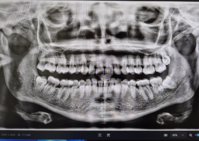

Ај ве молам кажете, сите 4ри осмици ли треба да се вадат?

Прикачени фајлови: